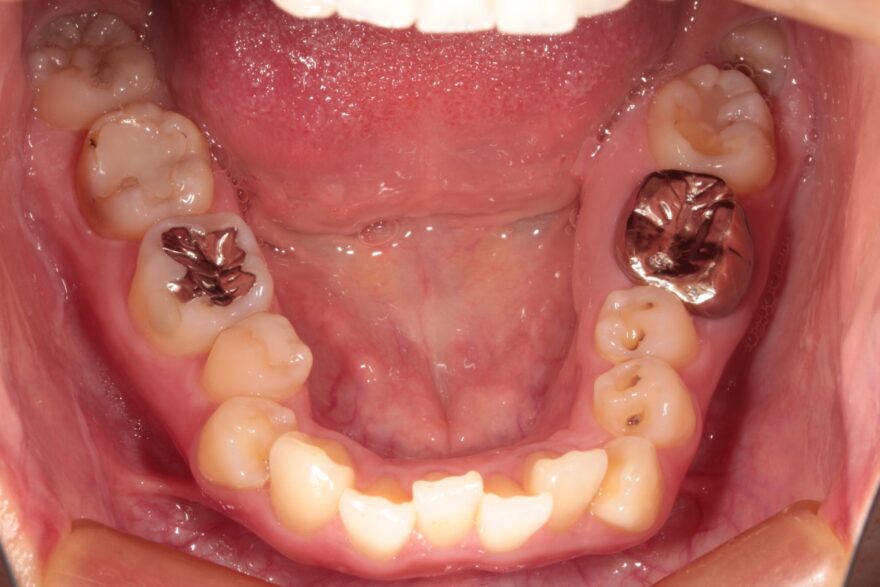

上下の変化はこちら!

凄くきれいに整ったと思いませんか??